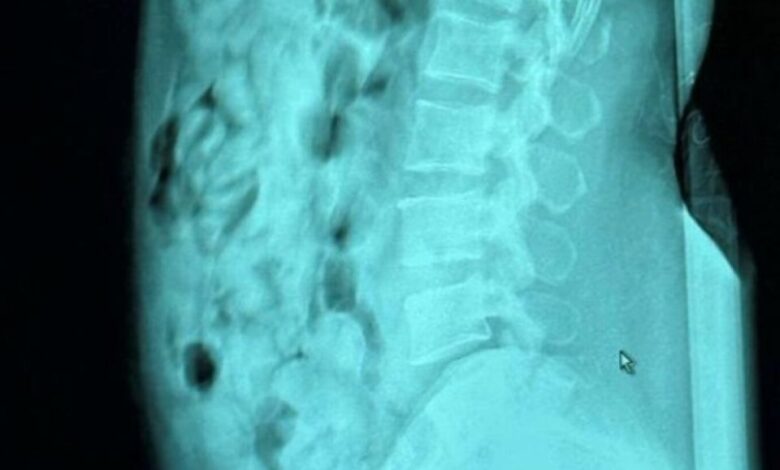

Ακτινολογικές εξετάσεις που πραγματοποιήθηκαν στο νοσοκομείο του Μπέργκαμο επιβεβαίωσαν ότι η γυναίκα είχε καταπιεί 120 σφαιρίδια, σχεδόν 1.393 γραμμαρίων ηρωίνης και τα οποία ήταν σφραγισμένα με κολλητική ταινία με προορισμό τη Σαρδηνία.

Η ακτινογραφία της 46χρονης που κατάπιε τις 120 αμπούλες ηρωίνης